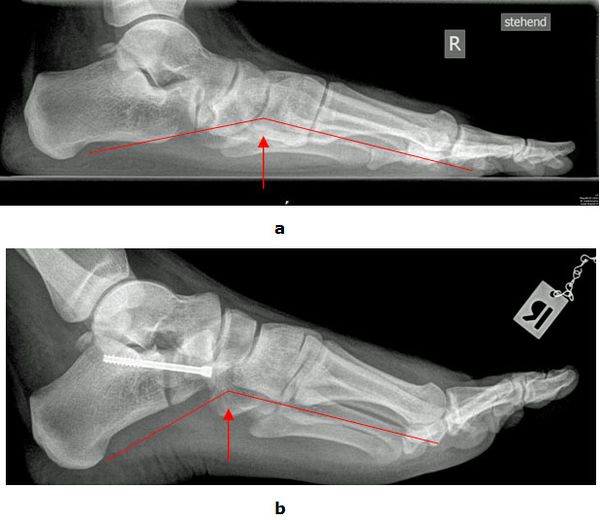

Abb.7: a Erhöhte Fußwölbung und Spitzfußstellung vor der Operation. b Wiederherstellung der Fußform postoperativ

Trotz erheblicher Fehlstellungen können Patienten mit geringen Beschwerden zunächst mit speziellen Einlagen (Stufeneinlage) und/oder orthopädischen Schuhen versorgt werden. Bei starken Beschwerden bedarf es einer operativen Korrektur des Fußes. Die Hohlfußdeformität wird am Scheitelpunkt der Fehlstellung durch die Entnahme eines Knochenkeils korrigiert. Liegt eine zusätzliche Steilstellung des ersten Strahls vor folgt eine zusätzliche Keilentnahme an der Basis des ersten Mittelfußknochens. Durch Eingriffe an den Sehnen werden die Krallenzehen behandelt und die muskuläre Balance des Fußes wieder hergestellt.

Abb.8: a Wiederherstellung der Fußwölbung vor und

b nach der Operation im seitlichen Röntgenbild